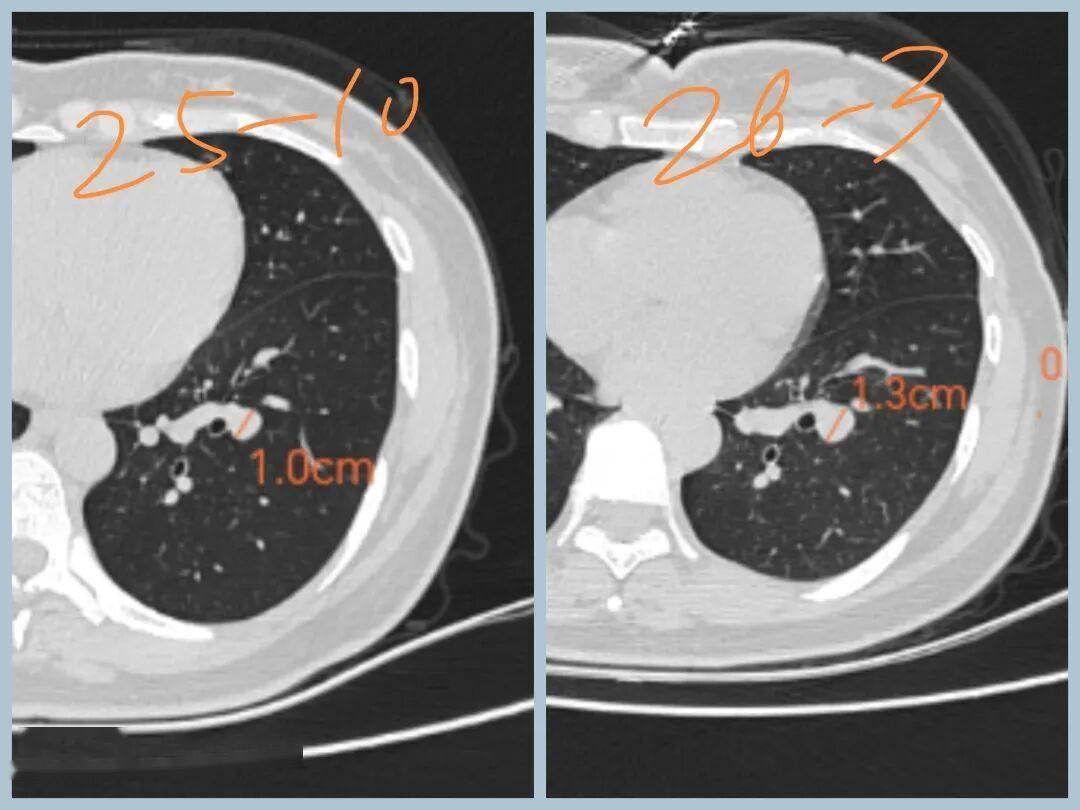

2026年3月CT示病变1.6cm

术前CT示:左肺下叶基底段实性结节,大小1.6cm,边界清,有浅分叶,内部密度不均,有点状高密度。看形态确实像良性。

最终病灶被顺利剥除,病理为错构瘤,下叶完整保留,非常NICE!